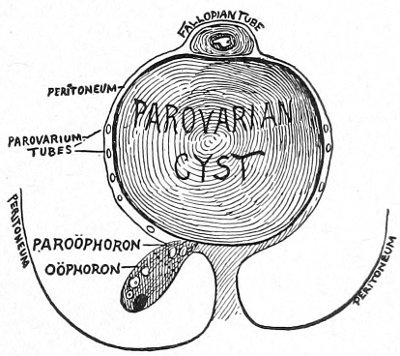

The origin of vaginal cysts has been much disputed. It is probable that they arise from the remains of the Wolffian canal—the canal of Gärtner. In the embryo the transverse or longitudinal tubule of the parovarium extends to the side of the uterus and thence down the side of the vagina to the urethral orifice. It persists in this condition in some of the lower animals—the sow and the cow—and may also persist as a closed tube in woman. In such cases it may become distended and form the vaginal cyst.